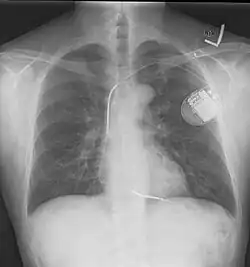

Ein ICD besteht im Prinzip aus zwei Komponenten. Einerseits dem ICD-Gerät, das aus der Steuerung, einer Batterie und einer Elektrode besteht, und einer venösen Elektrode, die in der rechten Herzkammer verankert wird. Der ICD wird unter der Haut vor oder in dem linken Brustmuskel implantiert. Der Diagnostikteil erkennt durch permanente EKG-Ableitung behandlungsbedürftige Störungen, der Stimulationsteil löst daraufhin den Stromstoß aus. Beim Schock wird ein elektrisches Feld aufgebaut.[5] Bei modernen Geräten kann dieses entweder zwischen der venösen Elektrode und dem Gehäuse des ICD-Geräts aufgebaut werden oder aber bei Verwendung sogenannter Dual-Coil-Elektroden (wie auf dem abgebildeten Röntgenbild) zwischen zwei getrennten Spulen einer venösen Elektrode. So kann je nach individueller Anatomie das elektrische Feld mit dem Ziel optimiert werden, möglichst viel Herzmuskelgewebe im elektrischen Feld zu erfassen.[6]